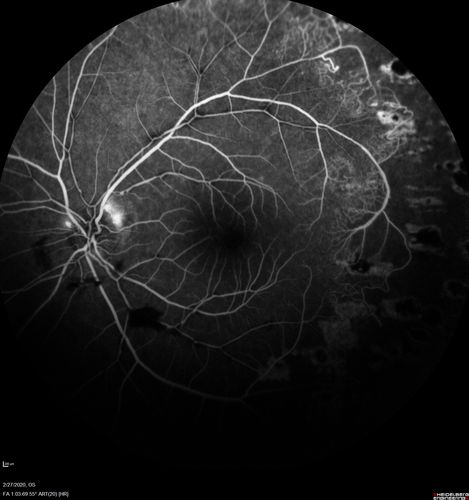

Eales Disease and fresh vitreous hemorrhage - 20 year old man

20 year old mane with fresh vitreous hemorrhage in the right eye.  At age 15 he had a PPV and laser in the left eye and laser in the right eye.  The vision is OD 20/80 PH 20/25, OS 20/25.  The left eye has a mild cataract.  He had prior testing for coagulopathies which was negative.  Testing done for syphillis and TB was negative.  Additional laser was done to prevent further bleeding in the right eye.